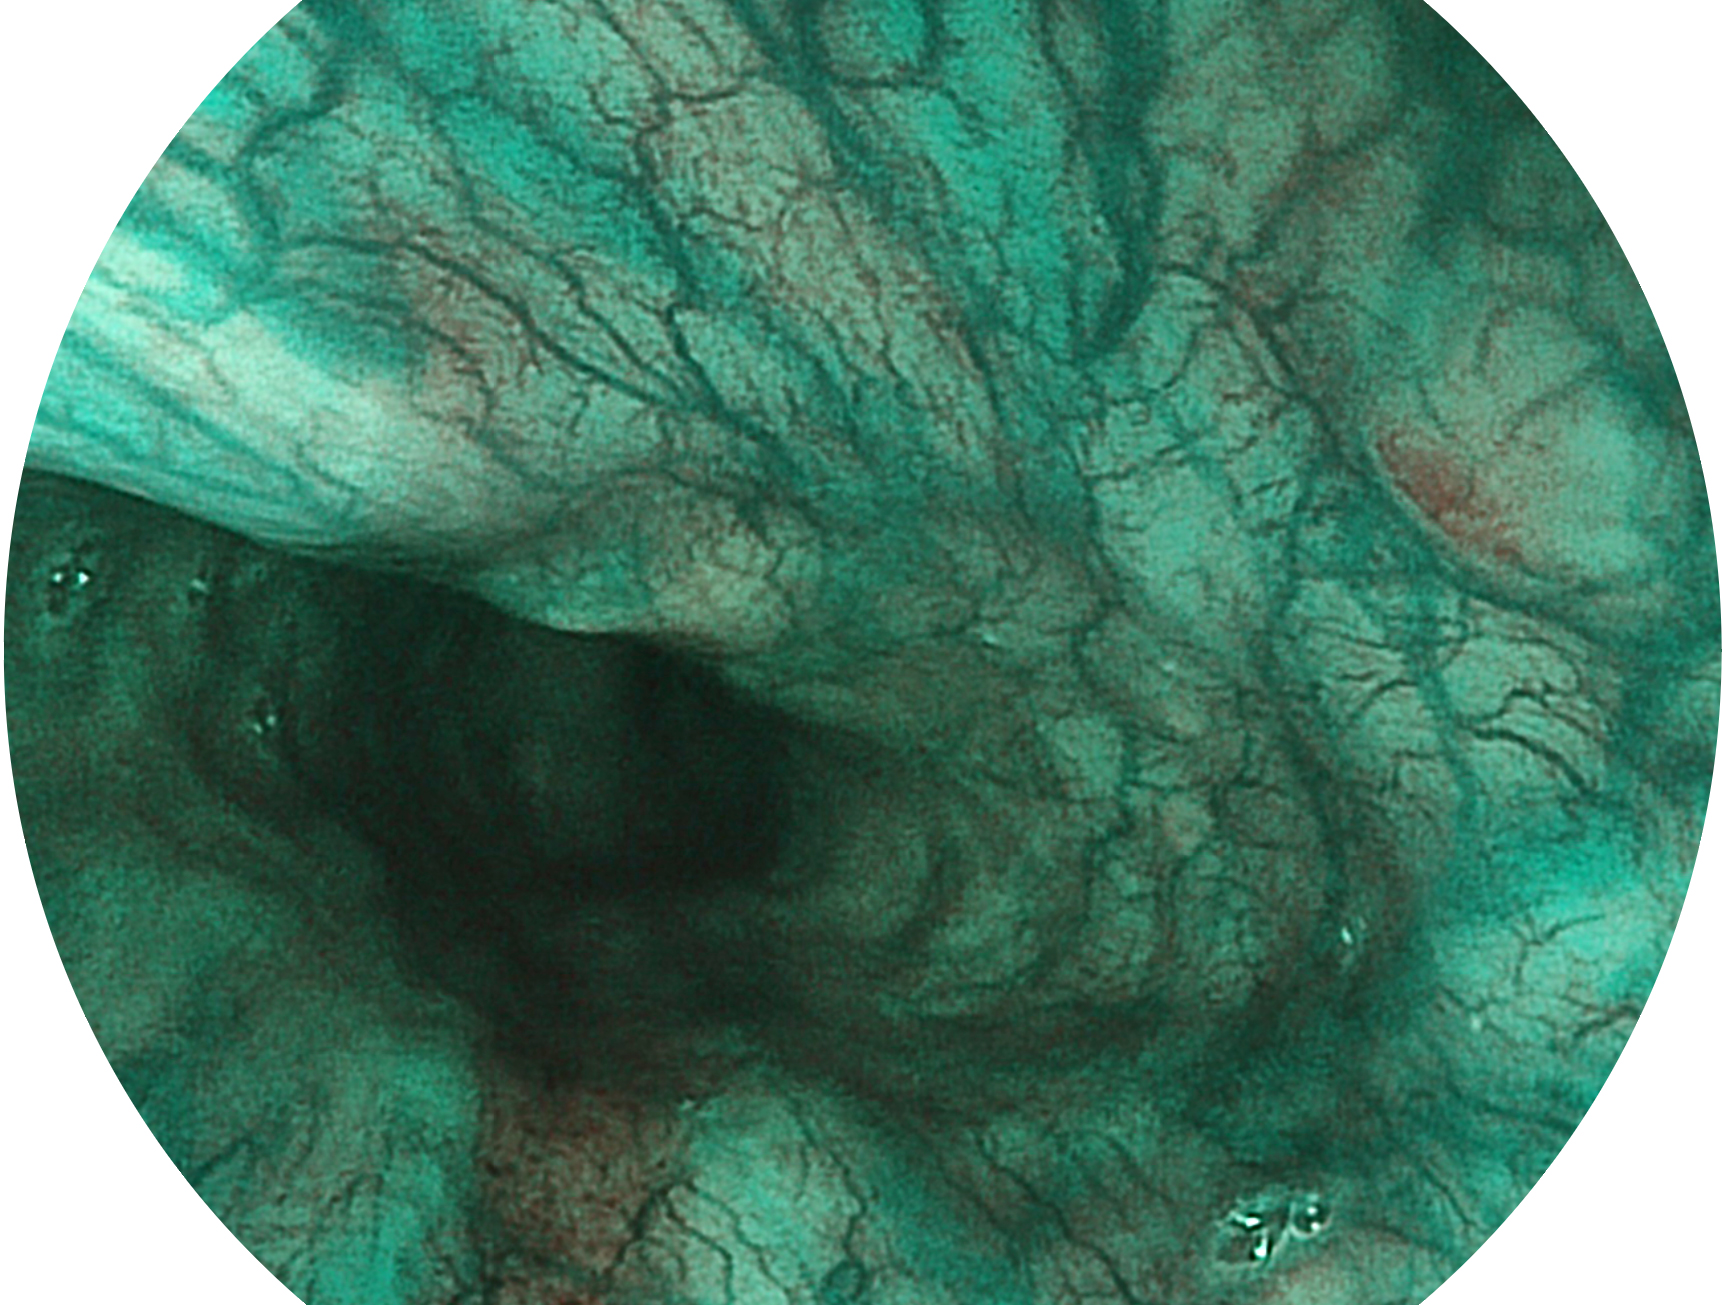

SFI技术是结合特定光谱照明与数字光谱滤波,实现高亮度特殊光成像。染色模式下,不改变粘液、食物残渣、粪液等基本颜色,在保持与白光照明相似的图像色调的同时突显了图像颜色的红白对比度,且在远距离观察的情况下具备与普通白光模式相同的图像亮度,有助于消化道疾病的大范围扫查和早癌筛查。

• 白光图像 SFI图像